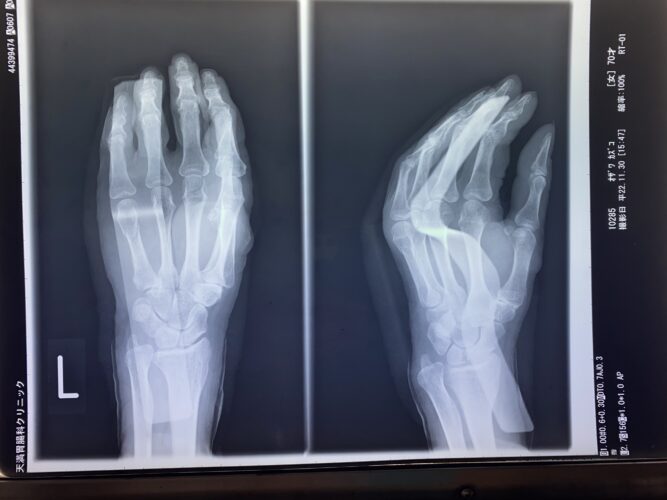

第5中手骨骨折(ボクサー骨折)でお悩みの方へ|手術以外の選択肢と接骨院で…